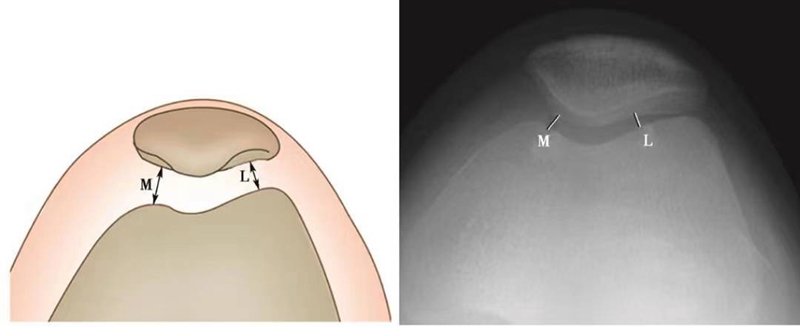

(4)髌股指数(patellofemoral index)的测量(图8):

髌股指数即髌骨-股骨内侧关节面间隙的最小间距(M)与髌骨-股骨外侧关节面间隙最小间距的比值(L)。正常情况下此值应<1.6,若髌股指数>1.6提示髌骨倾斜或(和)髌骨外侧半脱位。

图8 髌股指数的测量